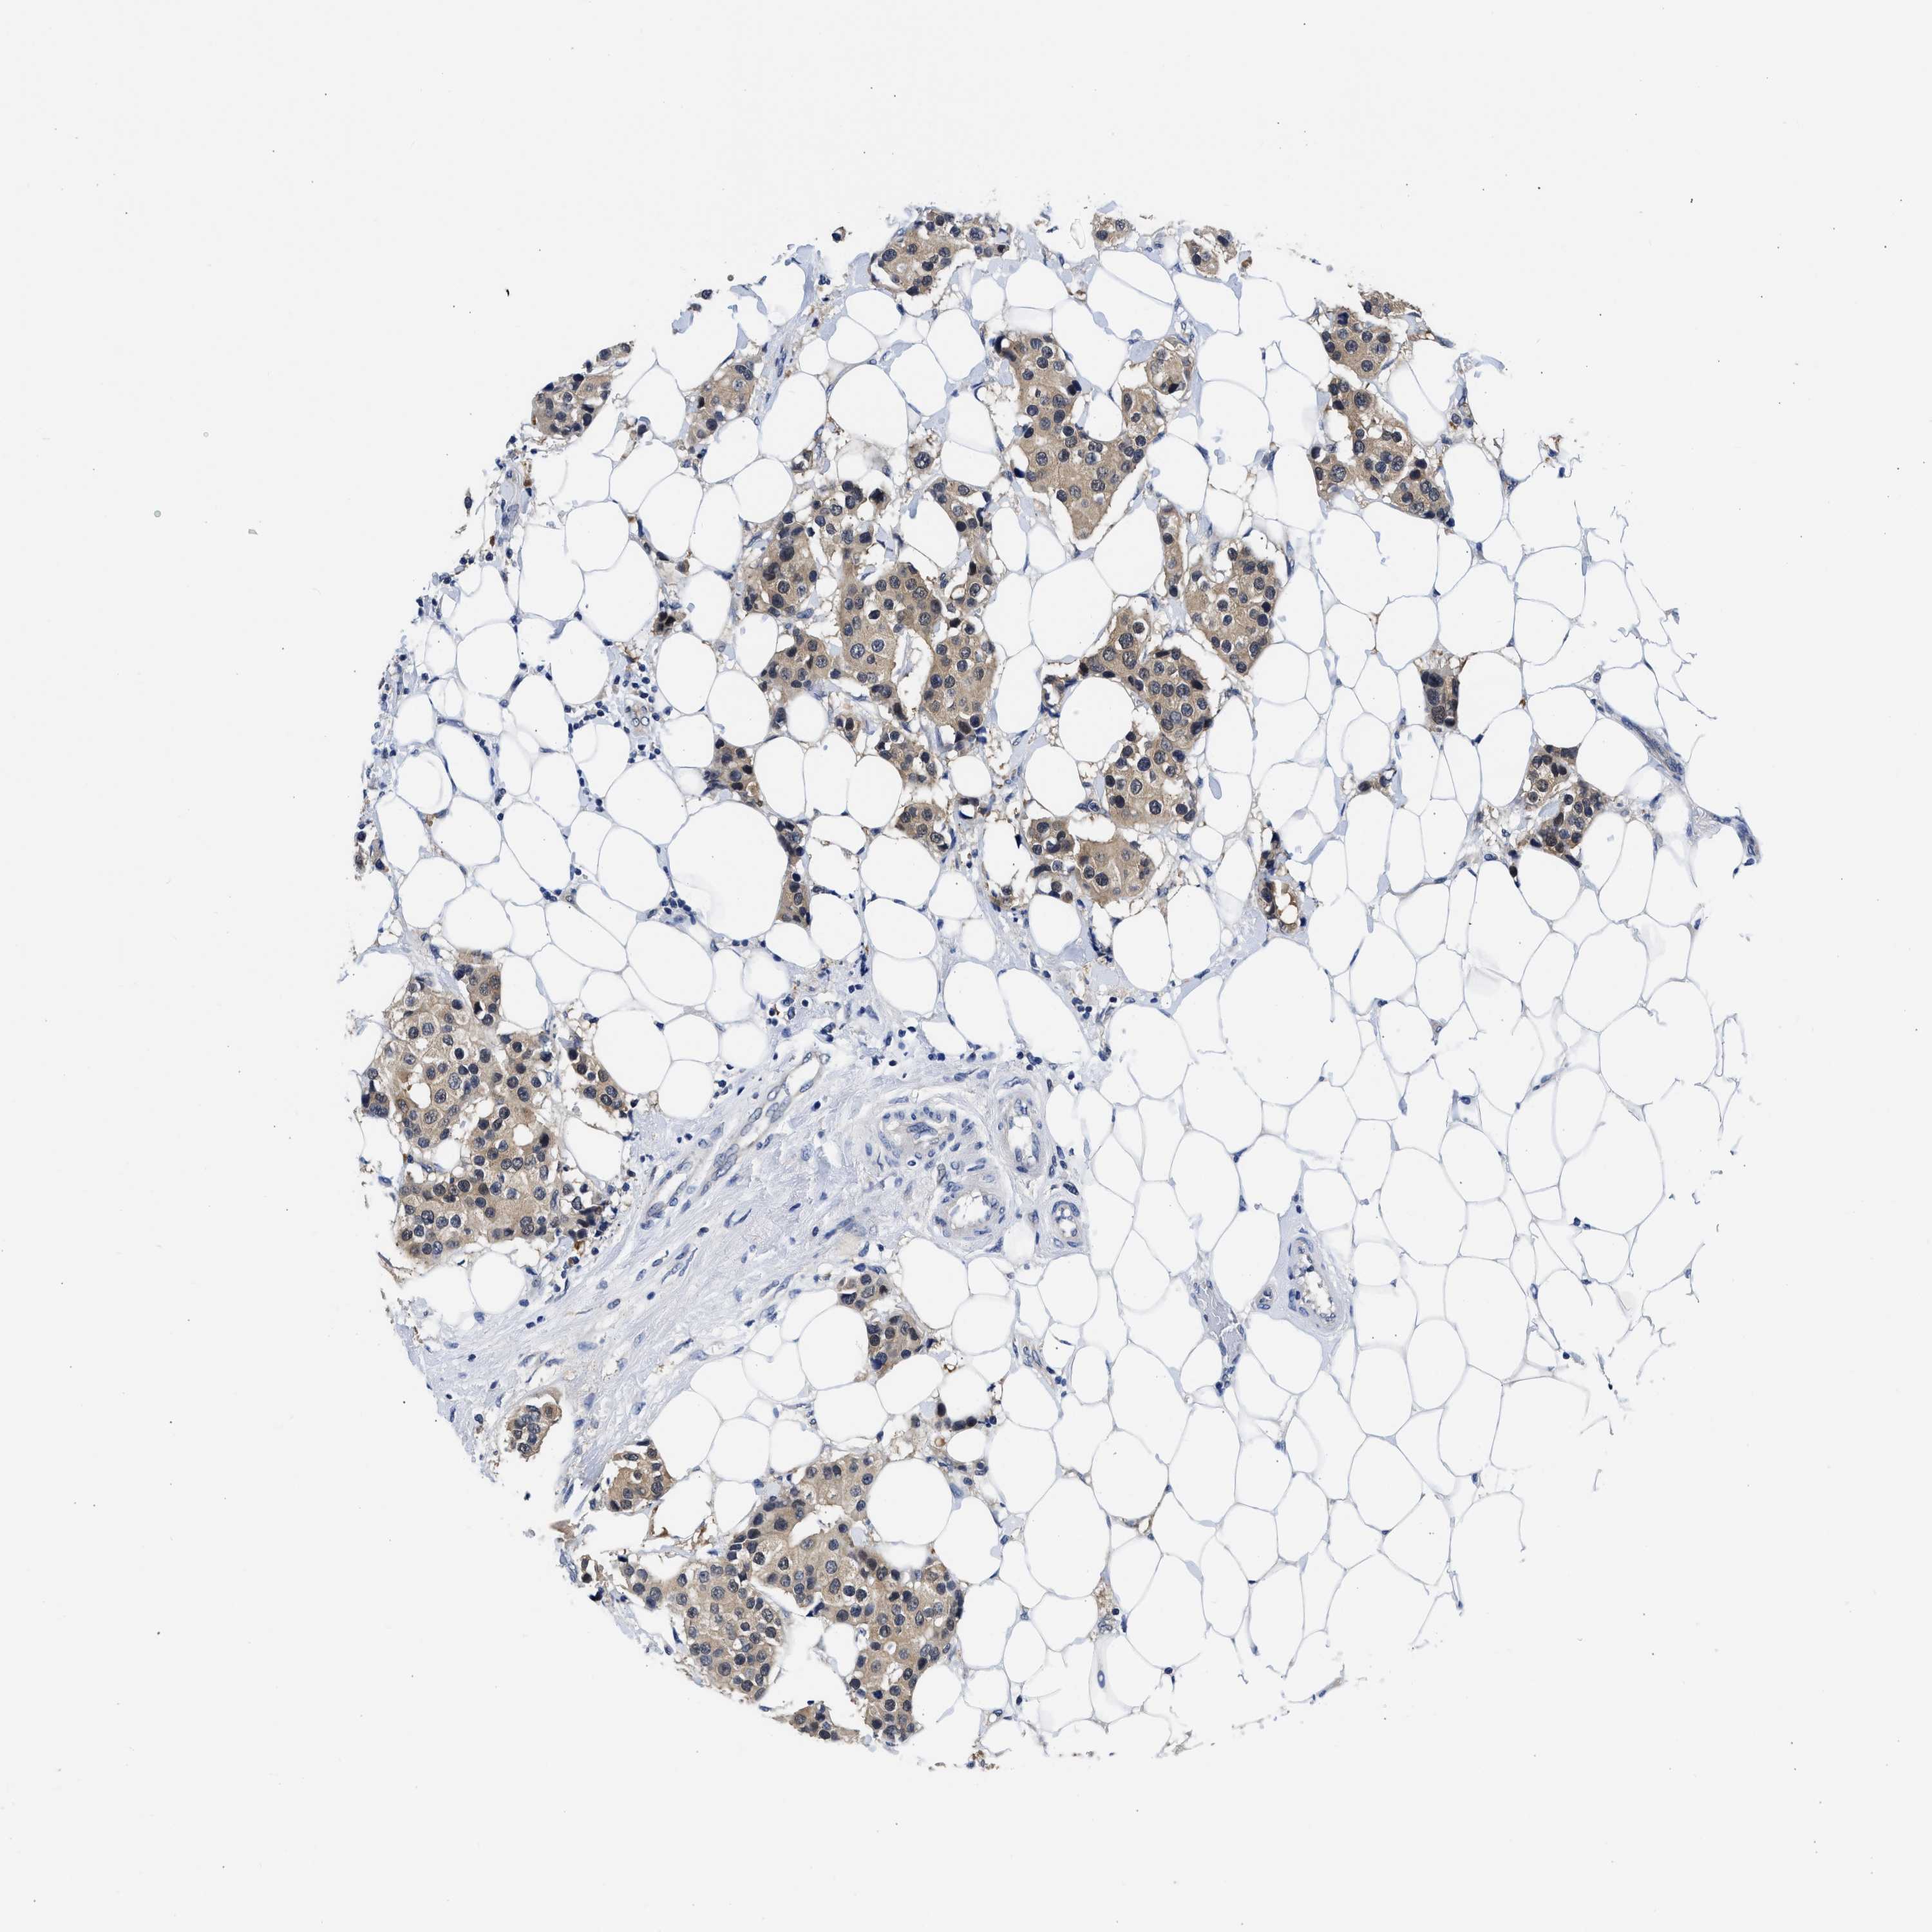

CANCER BREAST CANCER Show tissue menu

BRCA TCGA BRCA VALIDATION PROTEIN EXPRESSION